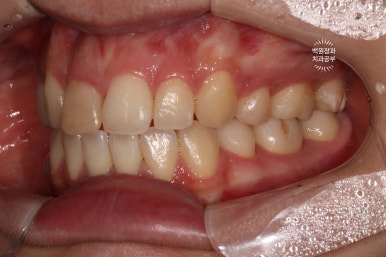

왼쪽: 우측 측면사진, 오른쪽: 좌측 측면사진

고개를 돌려 촬영한 사진을 보시면, 더욱 확실히 확인이 가능하실거에요.

우측 측면사진에 앞니가 하나 부족합니다. 정확히 얘기하면 대문니 - 중절치가 없죠.

교합면에서 보면, 앞니가 다섯개라는 것이 더 명확해집니다!!!

아마, 어렸을 때 앞니를 잃어버리신 것 같아요. 그래서 작은 어금니도 비대칭으로 왼쪽은 1개 오른쪽은 2개였습니다. 상당히 난이도 있는 교정치료일텐데, 정말 훌륭한 치료결과이긴 했었어요!